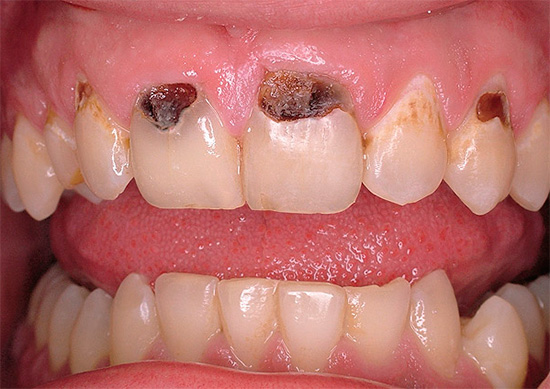

A foto abaixo mostra um exemplo típico de cárie cervical nos dentes da frente:

Ao mesmo tempo, surgem muitas perguntas sobre as causas de tais problemas e, é claro, sobre possíveis métodos para eliminar a cárie cervical, que discutiremos mais adiante.

Muitas pessoas começam a levar a cárie cervical a sério e as razões que a causam somente quando o problema é claramente evidente no reflexo no espelho e causa inconvenientes estéticos naturais. A zona de sorriso para pessoas que precisam de comunicação para implementar determinadas tarefas é de particular valor. E como a cárie cervical geralmente é localizada precisamente nos dentes da frente, há uma necessidade urgente de devolver o componente estético.